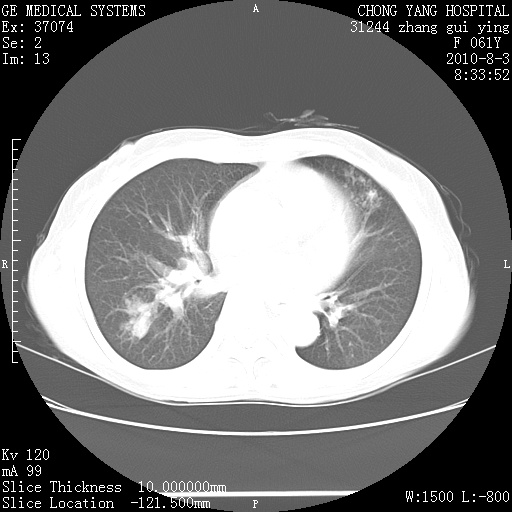

标题: CT28314:F61Y胸部增强,发热咳嗽一周入院,后面的为一周前平

1、支持考虑右侧中央型肺癌伴右肺中叶节段性不张及下叶支气管黏液痰栓    2、左肺上叶舌段感染。

双肺感染性病变,不除外合并结核感染。

确切的说:1:右肺下叶中心型肺癌侵及中叶支气管并中叶不张,纵膈淋巴结转移。2:左肺舌叶炎症。3:右侧胸腔少量积液

右肺下叶内基底段近膈不规则肿块,考虑右肺下叶周围型肺癌可能性大。